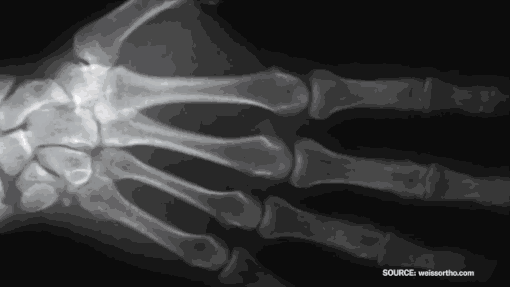

各种关节疾病其实是因为

体内的氨糖、钙、骨胶原流失引起的

从本质上而言,关节的各种问题是

随着年龄增加

氨糖,骨胶原,钙,镁等

各种骨骼所需营养大量流失引起的

缺乏这些形成骨骼的必需元素

受损的关节就无法修复